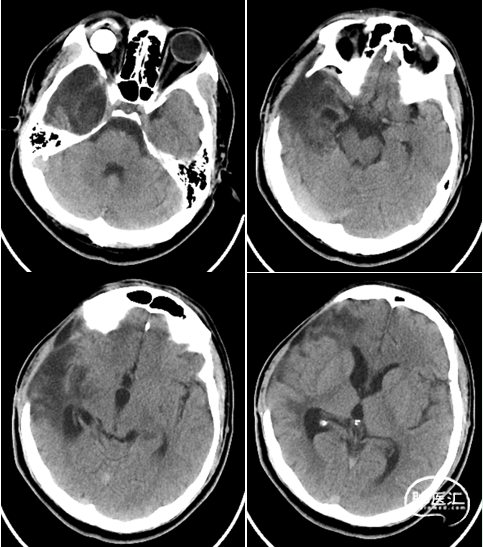

术后即时影像

血管造影影像

出院时影像